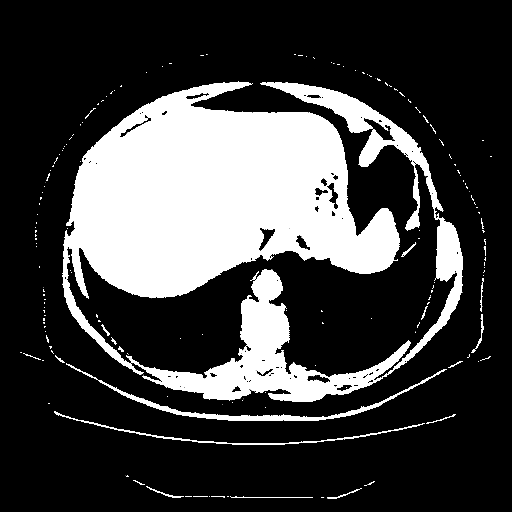

Original VENOUS CT scan

Full window (WL 1023.5, WW 4095 β†’ Low βˆ’1024, High +3071)

Actual HU range: [-1024.0, 3071.0]